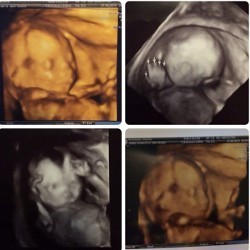

Kebahagiaan tengah menyelimuti pasangan Gisella Anastasia dan Gading Marten. Siang ini, Gisel siap melahirkan anak pertamanya secara caesar.